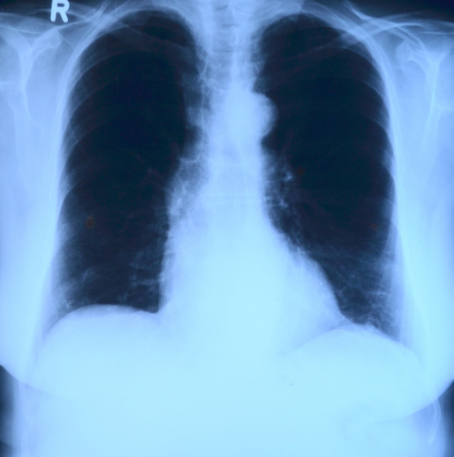

폐렴 백신은 우리 건강에 대한 중요한 투자 중 하나입니다. 폐렴은 심각한 호흡기 질환 중 하나로, 우리 생활 속에서 피할 수 없는 위협입니다. 이 블로그에서는 왜 폐렴 백신을 맞아야 하는지 그 중요성에 대해 알아보고자 합니다.

폐렴은 공기 중에 존재하는 세균 또는 바이러스를 통해 감염되는 심각한 호흡기 질환입니다. 이 질병은 기침, 가래, 고열 및 호흡곤란과 같은 다양한 증상을 유발할 수 있습니다. 폐렴은 특히 어린 아이, 노인, 만성질환 환자 및 면역곤란 환자들에게 위험합니다. 폐렴은 심각한 경우 호흡 곤란과 사망으로 이어질 수 있으므로 폐렴의 위험성을 인지하는 것이 중요합니다.